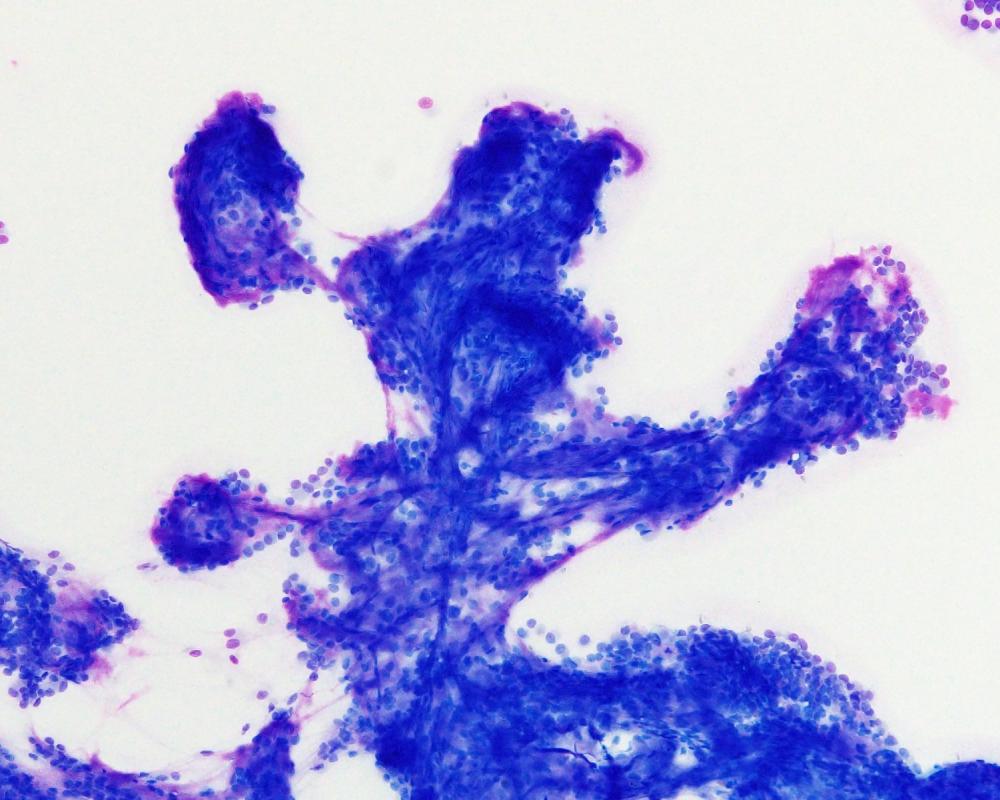

第40回日本臨床細胞学会九州連合会学会(大分)スライドカンファレンス症例1

種別:婦人科

出題:橋口 真理子 佐賀大学医学部病因病態科学講座

| 年齢 | 10代 | 性別 | 女性 |

| 採取部位 | 右卵巣腫瘍 | 採取方法 | 捺印細胞診 |

現病歴 手術の2か月前頃から腹部膨満感を自覚し近医受診。腹部エコーで骨盤内に17㎝大の充実性腫瘤を指摘され当院受診。右側卵巣腫瘍の診断で手術が施行された。右付属器切除術が行われ、術中迅速に提出された。右卵巣は20㎝程度に腫大し、割面は黄白色調で充実性腫瘤であった。捺印細胞診を採取した。

術前の採血では、hCG329mIU/ml (1.0 以下)、AFP3.3ng/ml(0~7.0)、CA125 92 U/ml (0-35)、LDH 2772U/L (124-222)であった。

| 正解 | 2.Dysgerminoma |

▼選択肢及び投票結果

| 1.Yolk sac tumor | 17件 | (16.2%) | |

| 2.Dysgerminoma | 77件 | (73.3%) | |

| 3.Granulosa cell tumor | 2件 | (1.9%) | |

| 4.Clear cell carcinoma | 7件 | (6.7%) | |

| 5.Neuroendocrine carcinoma | 2件 | (1.9%) | |

| 投票総数 | 105件 | (100%) |